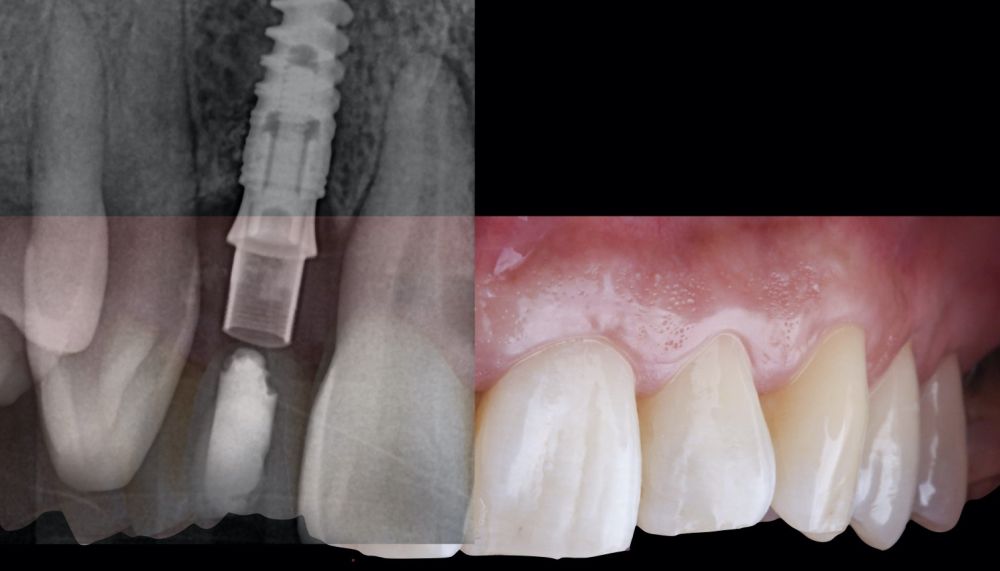

* Phase III: three months after implant placement, the soft tissue condition was favourable (Figures 5 and 6). A digital impression was obtained using an intraoral scanner for the fabrication of a screwretained

polymethyl methacrylate (PMMA) provisional restoration. Regarding the definitive

implant crown, a cement-screw-retained

restoration was fabricated with a titanium nitride interface, adapting the design to the emergence profile already consolidated with the provisional prosthesis. The crown was produced by CAD-CAM in zirconia with full reduction and feldspathic ceramic veneering for zirconia (Figure 7).

The final clinical outcome was satisfactory, fulfilling the patient’s aesthetic requirements. The soft tissues were morphologically and dimensionally stable, with no signs of

inflammation. However, changes in the peri-implant soft tissue (vestibular volumetric thickness) were demonstrated both qualitatively and quantitatively (Figures 8 and 9). In the immediate postoperative period (T1), the mean gain obtained when comparing T0 to T1 was 0.88 ± 0.15 mm, with a maximum increase of 1.1 mm. When comparing T0– T2, a mean gain of 0.73 ± 0.23 mm was observed. That is,

a volume contraction of 0.16 mm occurred from the time of graft placement (T1) until one and a half months later (T2).